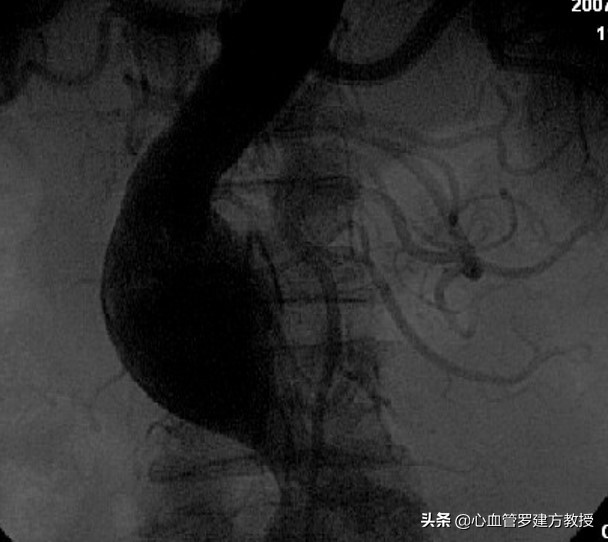

腹主动脉造影

腹主动脉造影发现,腹主动脉中段见一瘤样扩张约50-70mm*30-40mm,右肾动脉近段狭窄60-70%。最终诊断:腹主动脉瘤合并冠状动脉左主干+三支血管病变明确。